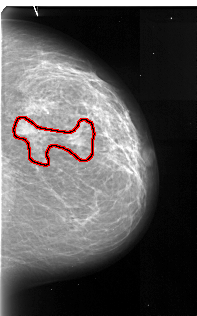

A_1056_1.RIGHT_MLO

RIGHT_CC LINES 4726 PIXELS_PER_LINE 2941 BITS_PER_PIXEL 16 RESOLUTION 42 OVERLAY

FILE: A_1056_1.RIGHT_CC.OVERLAY

TOTAL_ABNORMALITIES 1

ABNORMALITY 1

LESION_TYPE MASS SHAPE IRREGULAR MARGINS ILL_DEFINED

ASSESSMENT 4

SUBTLETY 5

PATHOLOGY MALIGNANT

TOTAL_OUTLINES 1

BOUNDARY